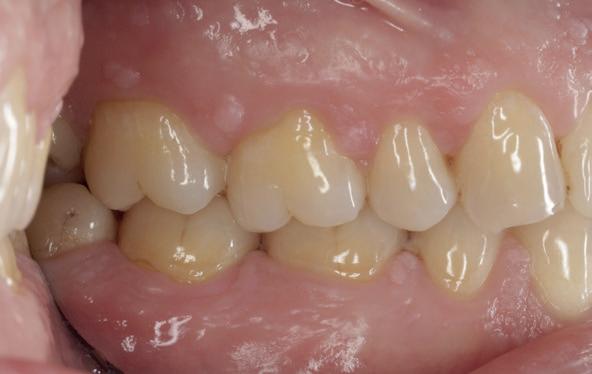

patiënt kon 2 maanden functioneren met de tijdelijke brug, waarna een kort consult werd gepland om te bespreken of hij tevreden was met de esthetiek en functie. Voor de patiënt hoefde niks veranderd te worden (afbeelding 11-14).

De technicus leverde op basis van de tijdelijke brug, de vast brug op implantaten af. Deze is van volledig zirkoonoxide met een titanium frame aan de binnenzijde voor de stevigheid (afbeelding 16-18). Een volledige brug van alléén zirkoonoxide is namelijk fractuur gevoelig. Na verwijderen van de tijdelijke brug kon de mondhygiëne van de patiënt gecontroleerd worden bij de implantaten. Patiënt hield het netjes schoon met een elektrische tandenborstel en een waterpik. Het is van belang dat de brug zonder spanning op zijn plek geduwd kan worden en deze niet kan kantelen op de abutments. Na het plaatsen van de brug werden de schroefjes getorqued op 15 Ncm, waarna de esthetiek, occlusie en articulatie gecontroleerd konden worden.

Daarna werden de schroefgaten gevuld met Blue M gel, teflon tape en composiet (afbeelding 19 en 20). Patiënt was zich zeer tevreden met het functionele en esthetische eindresultaat (afbeelding 19 en 20). Er was ook een nette hoektand en frontgeleiding. Voor de fonetiek werd een filmpje opgenomen, de F en de S werden netjes uitgesproken (afbeelding 21). De patiënt vervolgt zijn parodontale nazorg bij de mond-

hygiënist waarbij ook de mondhygiëne bij de brug wordt gecontroleerd. Op de OPT na 2 jaar (afbeelding 22) is het botniveau rondom de implantaten stabiel en is patiënt tevreden met zijn vaste brug.